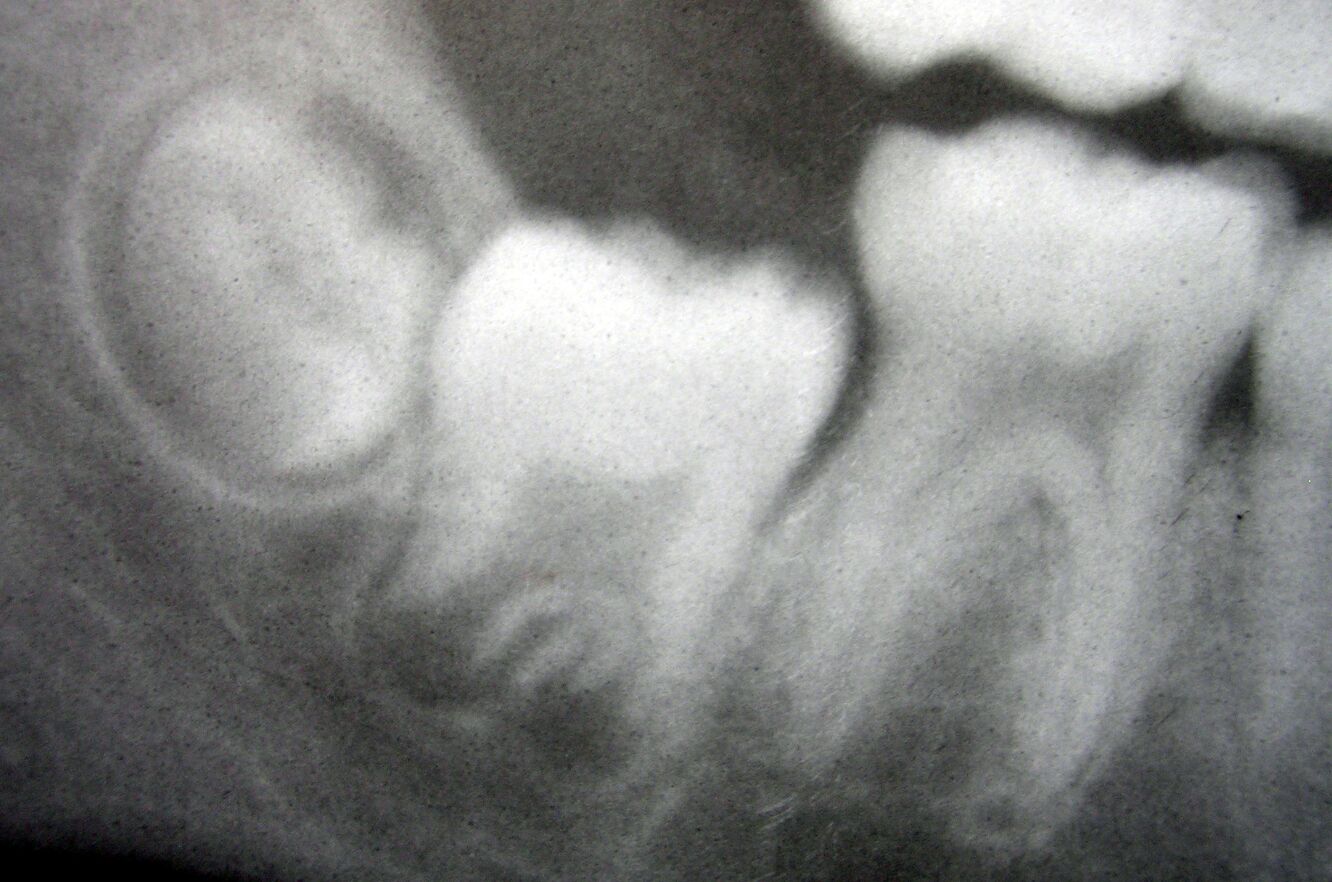

This dental radiograph provides a clear visualization of the lower right mandibular molars in varying developmental stages, captured in a periapical X-ray image. From left to right, the third molar (wisdom tooth), second molar, and first molar are visible, each representing different phases of dental development and eruption. The first molar, appearing fully erupted with complete root formation, contrasts with the second molar, which shows advanced but not complete development, while the third molar appears to be in an earlier stage of development and eruption. This radiographic presentation offers dental professionals and students valuable insights into the normal chronological development of permanent molars, their relative positions within the mandible, and the characteristic radiographic appearances that correspond to different developmental stages. Understanding these patterns is essential for age estimation, treatment planning in pediatric dentistry and orthodontics, and recognizing potential developmental anomalies that may require intervention.

The radiographic appearance of each molar in this image reflects these developmental timeframes. The differences in appearance demonstrate the progressive nature of tooth development.

Dental radiographs reveal distinctive features at each developmental stage that allow practitioners to assess normal progression or identify abnormalities. These features are clearly demonstrated in the image.

- The radiopaque crown structures (enamel and dentin) appear as bright white areas, while the pulp chambers and root canals present as radiolucent (darker) regions within the tooth structure.

- The surrounding periodontal ligament space appears as a thin radiolucent line around the roots, while the lamina dura (the thin layer of compact bone lining the socket) presents as a radiopaque line adjacent to this space.

Several key developmental markers are visible in the radiograph, providing information about the maturation status of each tooth. These markers help determine developmental age and potential concerns.

- The apical foramen status (open or closed) indicates the stage of root formation completion, with the first molar showing complete closure while the third molar apex remains widely open.

- The height of the alveolar bone crest around each tooth reflects the eruption status and periodontal health, showing progressive changes from the fully erupted first molar to the partially erupted third molar.

Distinguishing between normal variations and pathological findings requires thorough knowledge of typical developmental patterns. The radiograph demonstrates normal developmental variation.

- Root morphology normally varies between individuals and tooth types, with mandibular molars typically having two roots (mesial and distal) though additional roots or fused roots may represent normal variations.

- The pulp chamber and canal size naturally decrease over time due to secondary dentin formation, with younger teeth showing larger pulp spaces as visible in the developing third molar.

This radiographic image of mandibular molars at different developmental stages serves as an excellent reference for understanding the natural progression of dental development. The visualization of the third, second, and first molars side by side demonstrates the sequential nature of tooth formation and eruption that dental practitioners rely upon for numerous clinical assessments. From the fully developed first molar to the partially formed third molar, each tooth tells part of the developmental story, providing insights into approximate dental age and potential future concerns. For dental professionals, such radiographs are invaluable tools for patient assessment, treatment planning, and monitoring developmental milestones. They also serve as excellent educational resources for dental students learning to recognize the radiographic features associated with different developmental stages. Understanding these patterns enables more accurate diagnosis, improved treatment timing, and better recognition of developmental anomalies that may require intervention.